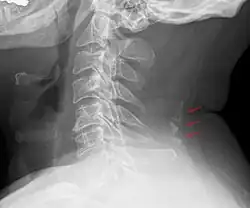

Auch beim Menschen finden sich gelegentlich – meist als Zufallsbefund im Röntgenbild der Halswirbelsäule – Verkalkungen im Ligamentum nuchae. Sie liegen meist auf Höhe der unteren Halswirbel oder des ersten Brustwirbel. Sie müssen dann gegen einen traumatischen Abriss am Dornfortsatz der Wirbel (Schipperfraktur) abgegrenzt werden.[1]